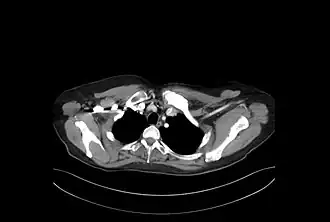

Description de l'image Hiperostosis EC.JPG.

Chacune de ces manifestations peut se présenter indépendamment des autres. Presque toutes les combinaisons sont possibles. Exemple Ostéite sur l'ensemble sterno-claviculaire et Pustulose palmo-plantaire.